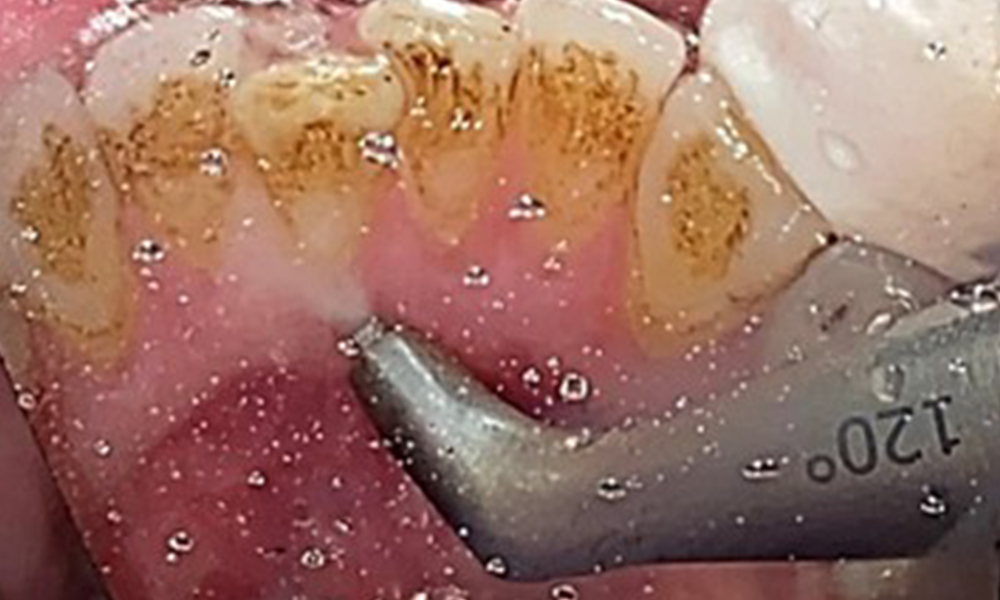

Due to the otherwise favourable general medical condition, the needs determined during the intraoral examination will be decisive for their treatment. It will be essential to periodically determine the probing depths. Gingival bleeding decreases in smokers, which is why the clinical diagnosis of periodontitis can only be made by probing (Fig. 7). Placing exclusive focus on the determination of bleeding indices may obscure existing periodontitis or gingivitis. (5)

Pocket probing (BOP) with depiction of tooth 36 lingual

Fig. 7 Pocket probing (BOP) with depiction of tooth 36 lingual, © Dr R. Krapf